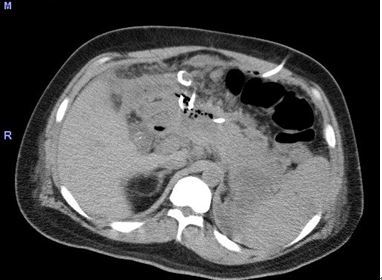

膿瘍に対するCTガイド下ドレナージ

- 重症膵炎後の腹腔内膿瘍に対するCTガイド下ドレナージ。大きな膿瘍がみられている。

CTガイド下に膿瘍を穿刺。